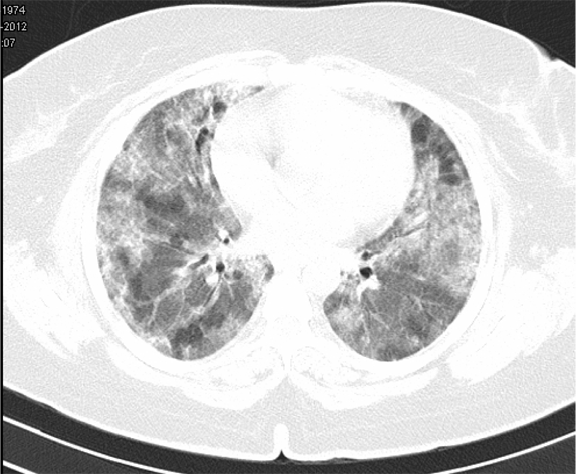

Subsequent investigations revealed corrected reticulocyte count 0.5%, microcytic hypochromic peripheral blood smear, low serum iron (36 μg/dL), low transferrin saturation (28%), normal Ferritin (140.2 ng/mL), normal total iron binding capacity (415 μg/dL) and normal serum vitamin B12 and folic acid levels. Her stool was negative for occult blood or parasites. Her serum creatinine was 0.8 mg/dL, blood urea was 36 mg/dL and urine microscopy was normal (no protein or red blood cells). The liver function tests and coagulation profile were within normal limits. Her retroviral status (HIV I and II by ELISA), hepatitis B surface antigen and hepatitis C antibody were negative. She received one pint blood transfusion in the ICU. Her chest X-ray (Figure 1) which was done in the ICU showed bilateral reticular infiltrates. Computed tomography (CT) scan of thorax was subsequently done which showed bilateral extensive ground glass opacities with interstitial thickening and nodules. (Figure 2) A provisional diagnosis of acute interstitial pneumonia/diffuse alveolar hemorrhage was made and she was started on broad spectrum antibiotics with high dose pulse steroids (Inj methylprednisolone 500 mg i.v. daily in divided doses for 3 days). Within 3 days she improved significantly and was weaned off the non invasive ventilator support. Later the steroids were tapered to oral prednisolone at 0.75 mg/kg body weight. Subsequently fibre optic bronchoscopy was done under local anesthesia with conscious sedation. Sequential broncho alveolar lavage (BAL) was done from right middle lobe, it showed increasing hemorrhagic returns of BAL aliquots and BAL counts showed 60% hemosiderophages, (Figure 3) confirming the diagnosis of diffuse alveolar hemorrhage. BAL was negative for gram stain and culture showing no evidence bacterial pathogens, acid fast bacilli, fungal organism, Fluorescent antibody stain for Pneumocystis jeroveci and cytology for cancer cells. Transbronchial lung biopsy was done from right middle and lower lobes. It showed interstitial fibrosis, hemosiderin laden macrophages in alveolar spaces and interstitium with positive Perl’s stain. (Figure 4) There was no evidence of vasculitis (capillaritis), granulomas, organising pneumonia and malignancy in the biopsy specimen. Her serum Rheumatoid factor (RF), antinuclear antibody (ANA), Double stranded Deoxyribonucleic acid (DsDNA), antiphospholipid antibody(APLA), Anti Glomerular Basement Membrane antibody (anti GBM) and anti U1 RNP were negative. Serum Complements (C3, C4 and Total Complement) and Antineutrophilic Cytoplasmic antibodies(c and p ANCA) were in normal range. After one week of treatment with steroids, she improved and there was no further drop in hemoglobin. At this time spirometry was done and it was normal. Her chest X-ray and CT thorax repeated after one month showed complete clearing of the shadows. (Figure 5)

Figure 2: Computed tomography scan of chest revealed ground glass opacities with diffuse interstitial opacities.